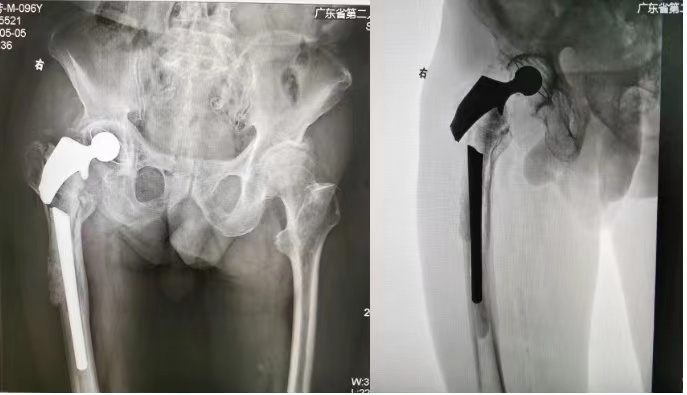

右侧全髋关节翻修术后X线显示髋关节假体断裂,断裂的假体穿出股骨,骨水泥固定的假体周围大量骨质缺损。

省二医关节骨科副主任(主持工作)、主任医师李贵涛指着曾老伯的影像资料说,曾老伯有严重的骨质疏松,骨质条件非常差;假体断裂并穿出股骨,继发了股骨部大量骨质缺损、骨溶解,情况严重且累及范围大;上次“翻修”时缩短手术时间、简化手术程序,采用了骨水泥固定假体,如何取出也是难题……